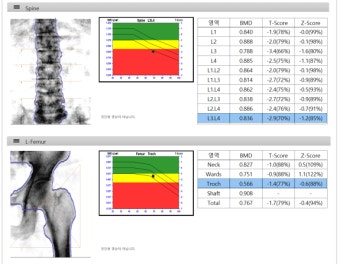

골밀도(BMD, Bone Mineral Density) 검사는 뼈 속의 미네랄 양을 측정하여 뼈의 강도를 판단하는 가장 중요한 검사입니다.

그중에서도 ‘T점수(T-score)’는 내 뼈의 상태를 직접적으로 보여주는 지표로, 치료 여부를 판단할 때 필수적인 기준이 됩니다.

T점수는 내 뼈 밀도를 20~30대 건강한 성인의 평균 뼈 밀도와 비교한 값입니다.

즉, ‘내 뼈가 이상적인 상태에 비해 얼마나 튼튼한지’를 나타내는 점수죠.